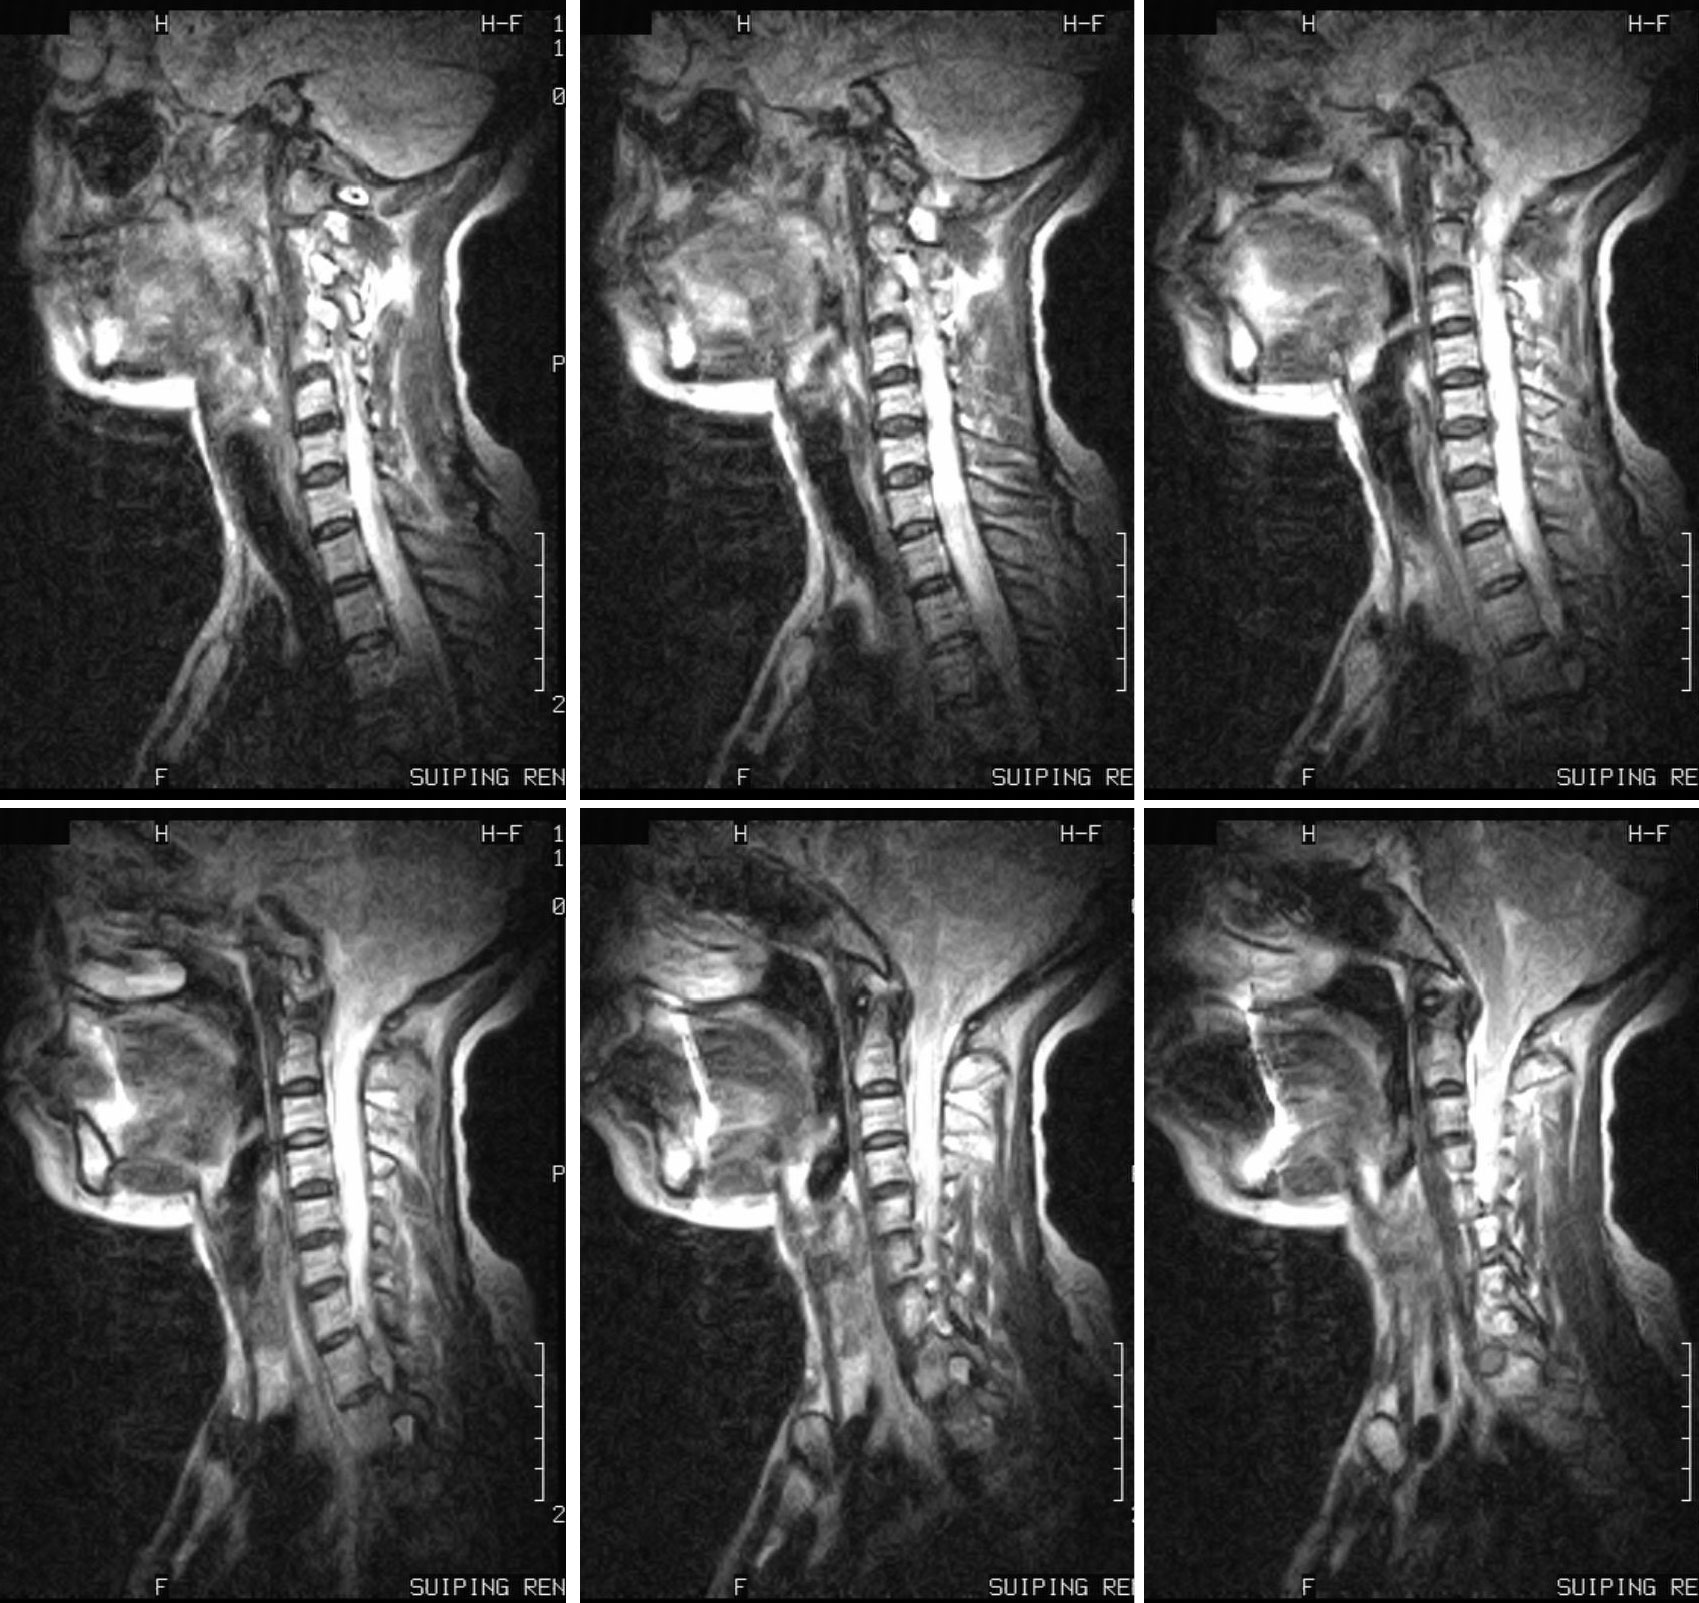

CHiari 畸形并脊髓空洞

女 46岁 因颈部不适,按颈椎病治疗无效。

本例楼主没有公布结果,大家一致的意见为:CHiari 畸形并脊髓空洞。